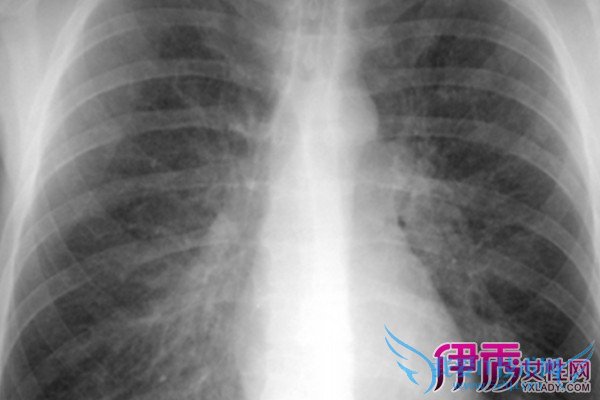

间质性肺病(Interstitial lung Disease,简称ILD) 是以弥漫性肺实质、肺泡炎和间质纤维化为病理基本改变,以活动性呼吸困难、X 线胸片示弥漫阴影、限制性通气障碍、弥散功能(DLCO)降低和低氧血症为临床表现的不同类疾病群构成的临床病理实体的总称。ILD 通常不是恶性的,也不是由已知的感染性致病源所引起的。继发感染时可有黏液浓痰,伴明显消瘦、乏力、厌食、四肢关节痛等全身症状,急性期可伴有发热。